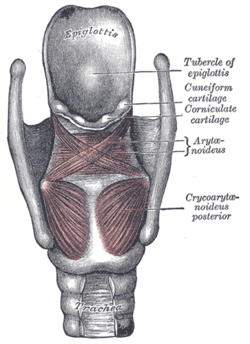

Muscles

The muscles of the larynx are divided into intrinsic and extrinsic muscles.

The intrinsic muscles are divided into respiratory and the phonatory muscles (the muscles of phonation). The respiratory muscles move the vocal cords apart and serve breathing. The phonatory muscles move the vocal cords together and serve the production of voice. The extrinsic, passing between the larynx and parts around; and intrinsic, confined entirely. The main respiratory muscles are the posterior cricoarytenoid muscles. The phonatory muscles are divided into adductors (lateral cricoarytenoid muscles, arytenoid muscles) and tensors (cricothyroid muscles, thyroarytenoid muscles).

Intrinsic

The intrinsic laryngeal muscles are responsible for controlling sound production.

- Cricothyroid muscle lengthen and tense the vocal folds.

- Posterior cricoarytenoid muscles abduct and externally rotate the arytenoid cartilages, resulting in abducted vocal folds.

- Lateral cricoarytenoid muscles adduct and internally rotate the arytenoid cartilages, increase medial compression.

- Transverse arytenoid muscle adduct the arytenoid cartilages, resulting in adducted vocal folds.[2]

- Oblique arytenoid muscles narrow the laryngeal inlet by constricting the distance between the arytenoid cartilages.

- Thyroarytenoid muscles - sphincter of vestibule, narrowing the laryngeal inlet, shortening the vocal folds, and lowering voice pitch. The internal thyroarytenoid is the portion of the thyroarytenoid that vibrates to produce sound.

Notably, the only muscle capable of separating the vocal cords for normal breathing is the posterior cricoarytenoid. If this muscle is incapacitated on both sides, the inability to pull the vocal folds apart (abduct) will cause difficulty breathing. Bilateral injury to the recurrent laryngeal nerve would cause this condition. It is also worth noting that all muscles are innervated by the recurrent laryngeal branch of the vagus except the cricothyroid muscle, which is innervated by the external laryngeal branch of the superior laryngeal nerve (a branch of the vagus).